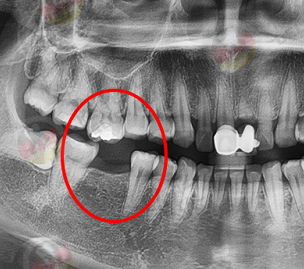

邻牙松动,再掉两颗:牙齿缺失位置形成的空缺会打乱本来整齐相互支撑、固定的牙齿状况,而缺牙导致邻牙失去了固定,相邻的两颗牙齿会向空缺位置倾斜,而且倾斜的情况是没有止境的,慢慢牙齿开始松动甚至脱落。

对牙伸长,再掉一颗:如果是下颌牙缺失,不仅是邻牙会倾斜,也会导致上颌牙失去了对咬牙,导致上颌牙向前伸长,严重的话会占据整个缺牙位置,到时候想要修复牙齿,连上颌牙也需要拔除才能修复。